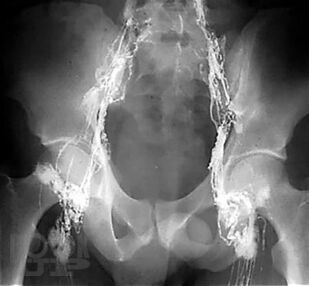

В учебном пособии в краткой и доступной форме излагаются современные сведения о строении лимфатической и иммунной систем. Латинская и русская анатомическая терминологии приведены в соответствии с Международной анатомической номенклатурой, принятой Федеративным комитетом по анатомической терминологии (FCAT, 1998). Учебное пособие включает опорные термины, необходимые при изучении соответствующих анатомических образований, а также тестовые задания и ситуационные задачи, что поможет обучающимся в освоении большого фактического материала при изучении путей транспорта лимфы, топографии регионарных групп лимфатических узлов и строения органов иммунной системы. Представлены современные методы визуализации лимфатической системы. Издание снабжено большим количеством схем и рисунков, взятых из открытых источников, что облегчает понимание организации лимфатической и иммунной систем.